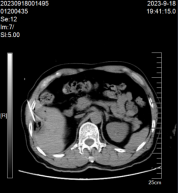

患者,林某某,男性,70岁,既往有乙肝病史,因体检发现肝脏占位入住我院肿瘤内科。入院后肝癌组团队医护立即完善相关检查,肝脏磁共振:肝Ⅵ段见团块状异常信号影,大小约为20mm×16mm×20mm,DWI呈高信号影,增强扫描呈不均匀强化(见图1)。甲胎蛋白(AFP) 1020.00IU/ml,AFP-L3甲胎蛋白异质体:31.20IU/ml,异常凝血酶原测定:341.00 mAU/mL。临床诊断为原发性肝癌,肝癌组卓曼云和张诚胜医生综合分析患者病情指出,患者诊断小肝癌明确,可选择微波消融或手术切除。患者家属考虑年纪大,不愿意手术治疗,遂在CT引导下行肝癌微波消融术。消融术中患者无手术出血,术后无明显不良反应,住院时间短,住院费用少,术后恢复快,1个月后复查肝脏MRI提示完全消融。目前患者定期复查未见复发。

消融前 消融中 消融后